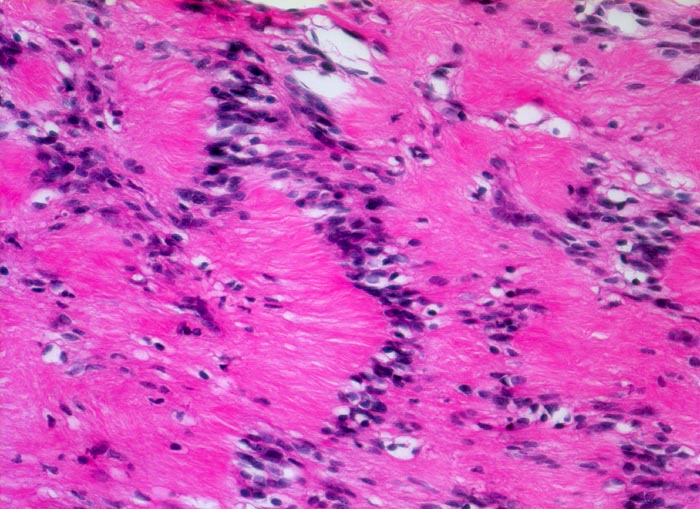

Schwannom: Verocay bodies

Palisadierung der Tumorzellkerne und parallele Anordnung der kernlosen Zellfortsätze in einem Verocay body.

Immunhistochemisch sind die Tumorzellen diffus und stark positiv für S-100 Protein.

Derber abgekapselter Tumor am Nervus ulnaris

Die parallele Anordnung von Zellkernen und Zytoplasmafortsätzen nennt man Verocay body. Diese sind typisch für Schwannome können aber auch von anderen Tumoren imitiert werden (z.B. Meningeom).